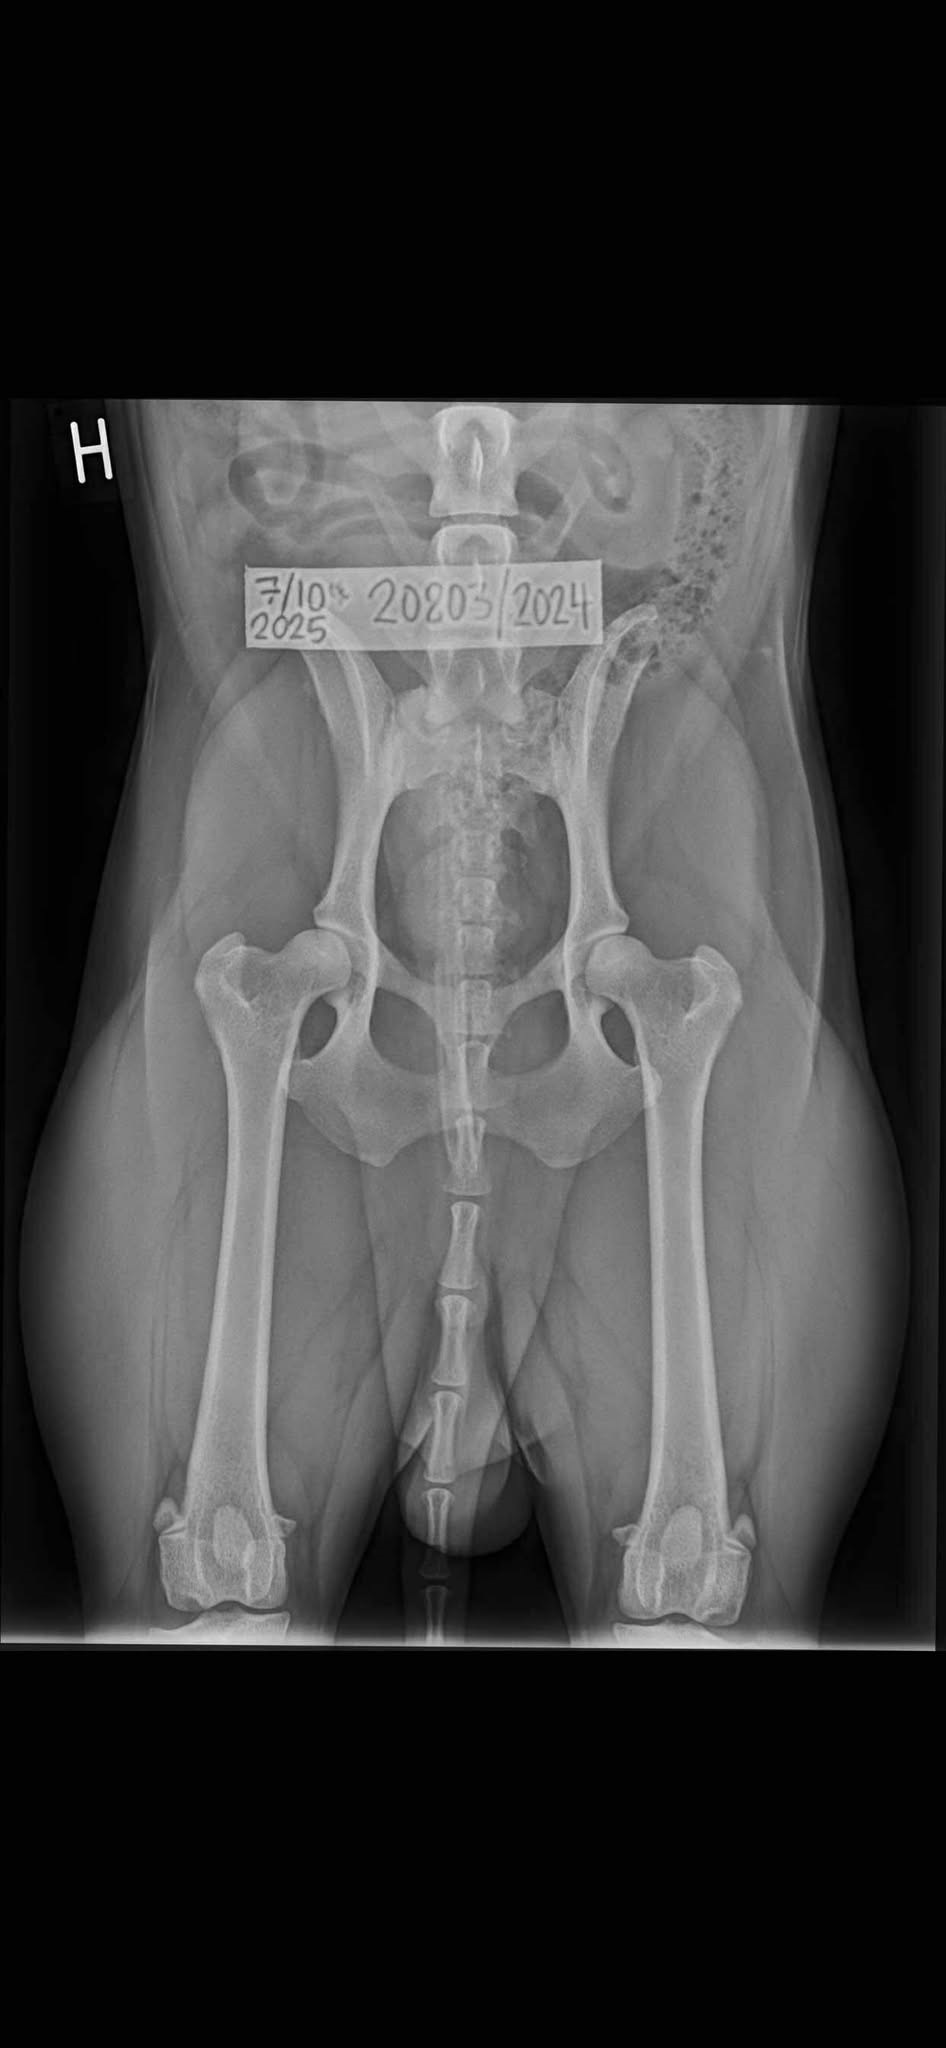

Bilden från omröntgen. Eftersom han varken var

ledslapp eller hade pålagringar någon av avläsningarna så förstår jag inte att

det inte blev bättre med denna raka och bra bild? Ffa. vänster (bildens höger)

ser omöjligt ut som D! Är hunden ledslapp så kan den

aldrig få ett bättre resultat, men det är inte Nile.

Kanske kan det bli Nordiska

panelen.